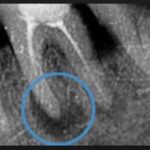

Хронический периодонтит зуба боли практически не вызывает, если речь идет о фиброзной форме. Только по рентгену можно диагностировать недуг. Ощущается тяжесть, подвижность пораженных зубов, их оттенок может меняться. Бывает так, что человек живет много лет с хронической формой и не подозревает об этом, поскольку визуального осмотра порой недостаточно для постановки диагноза. При обострении симптомы такие же, как при острой стадии

Проводится термопроба, которая при наличии заболевания отрицательная. Очаг воспаления часто малозаметен при внешнем осмотре. Поэтому обязателен рентген, позволяющий определить степень поражения и состояние больного зуба после периодонтита. По результатам исследований ставится диагноз, формируется терапевтический курс. Не стоит пытаться справиться с болезнью домашними средствами – недуг сложно поддается лечению даже при помощи действенных медикаментов.